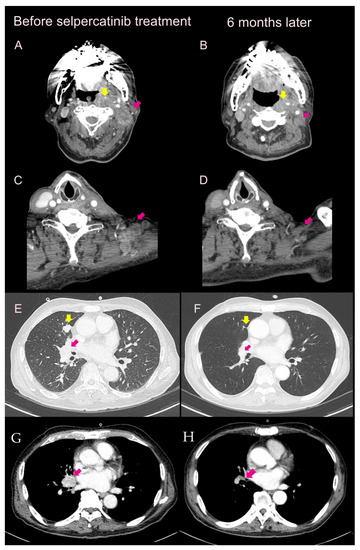

2.1. Case 1

2.2. Case 2

2.3. Case 3

2.4. Case 4